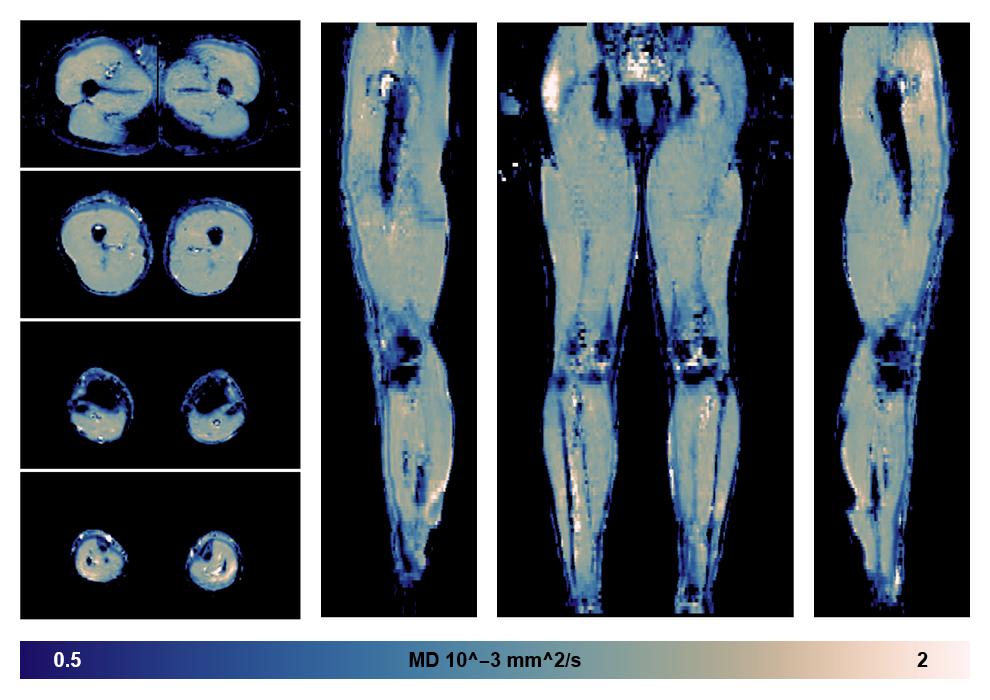

• Mean diffusivity

IVIM corrected whole leg muscle mean diffusivity obtained from diffusion tensor imaging.